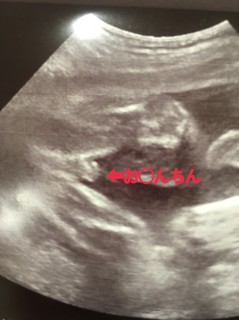

755グラム、元気な男の子です! 今日初めての4Dエコー撮ってきました! 両足で私のお腹をキックキック! 最後の出産から15年が経った今だからこそ進化したエコーを見られる事が出来て感動です。

性別の再確認!男の子でした。 830gと、標準でした! 一安心です。

4D撮ってもらいました!大きさも週数ど真ん中らしく順調とのこと(^^) エコー中はキックやパンチ、指しゃぶりなどの可愛い姿を見せてくれてくれました!8割男の子みたいです。